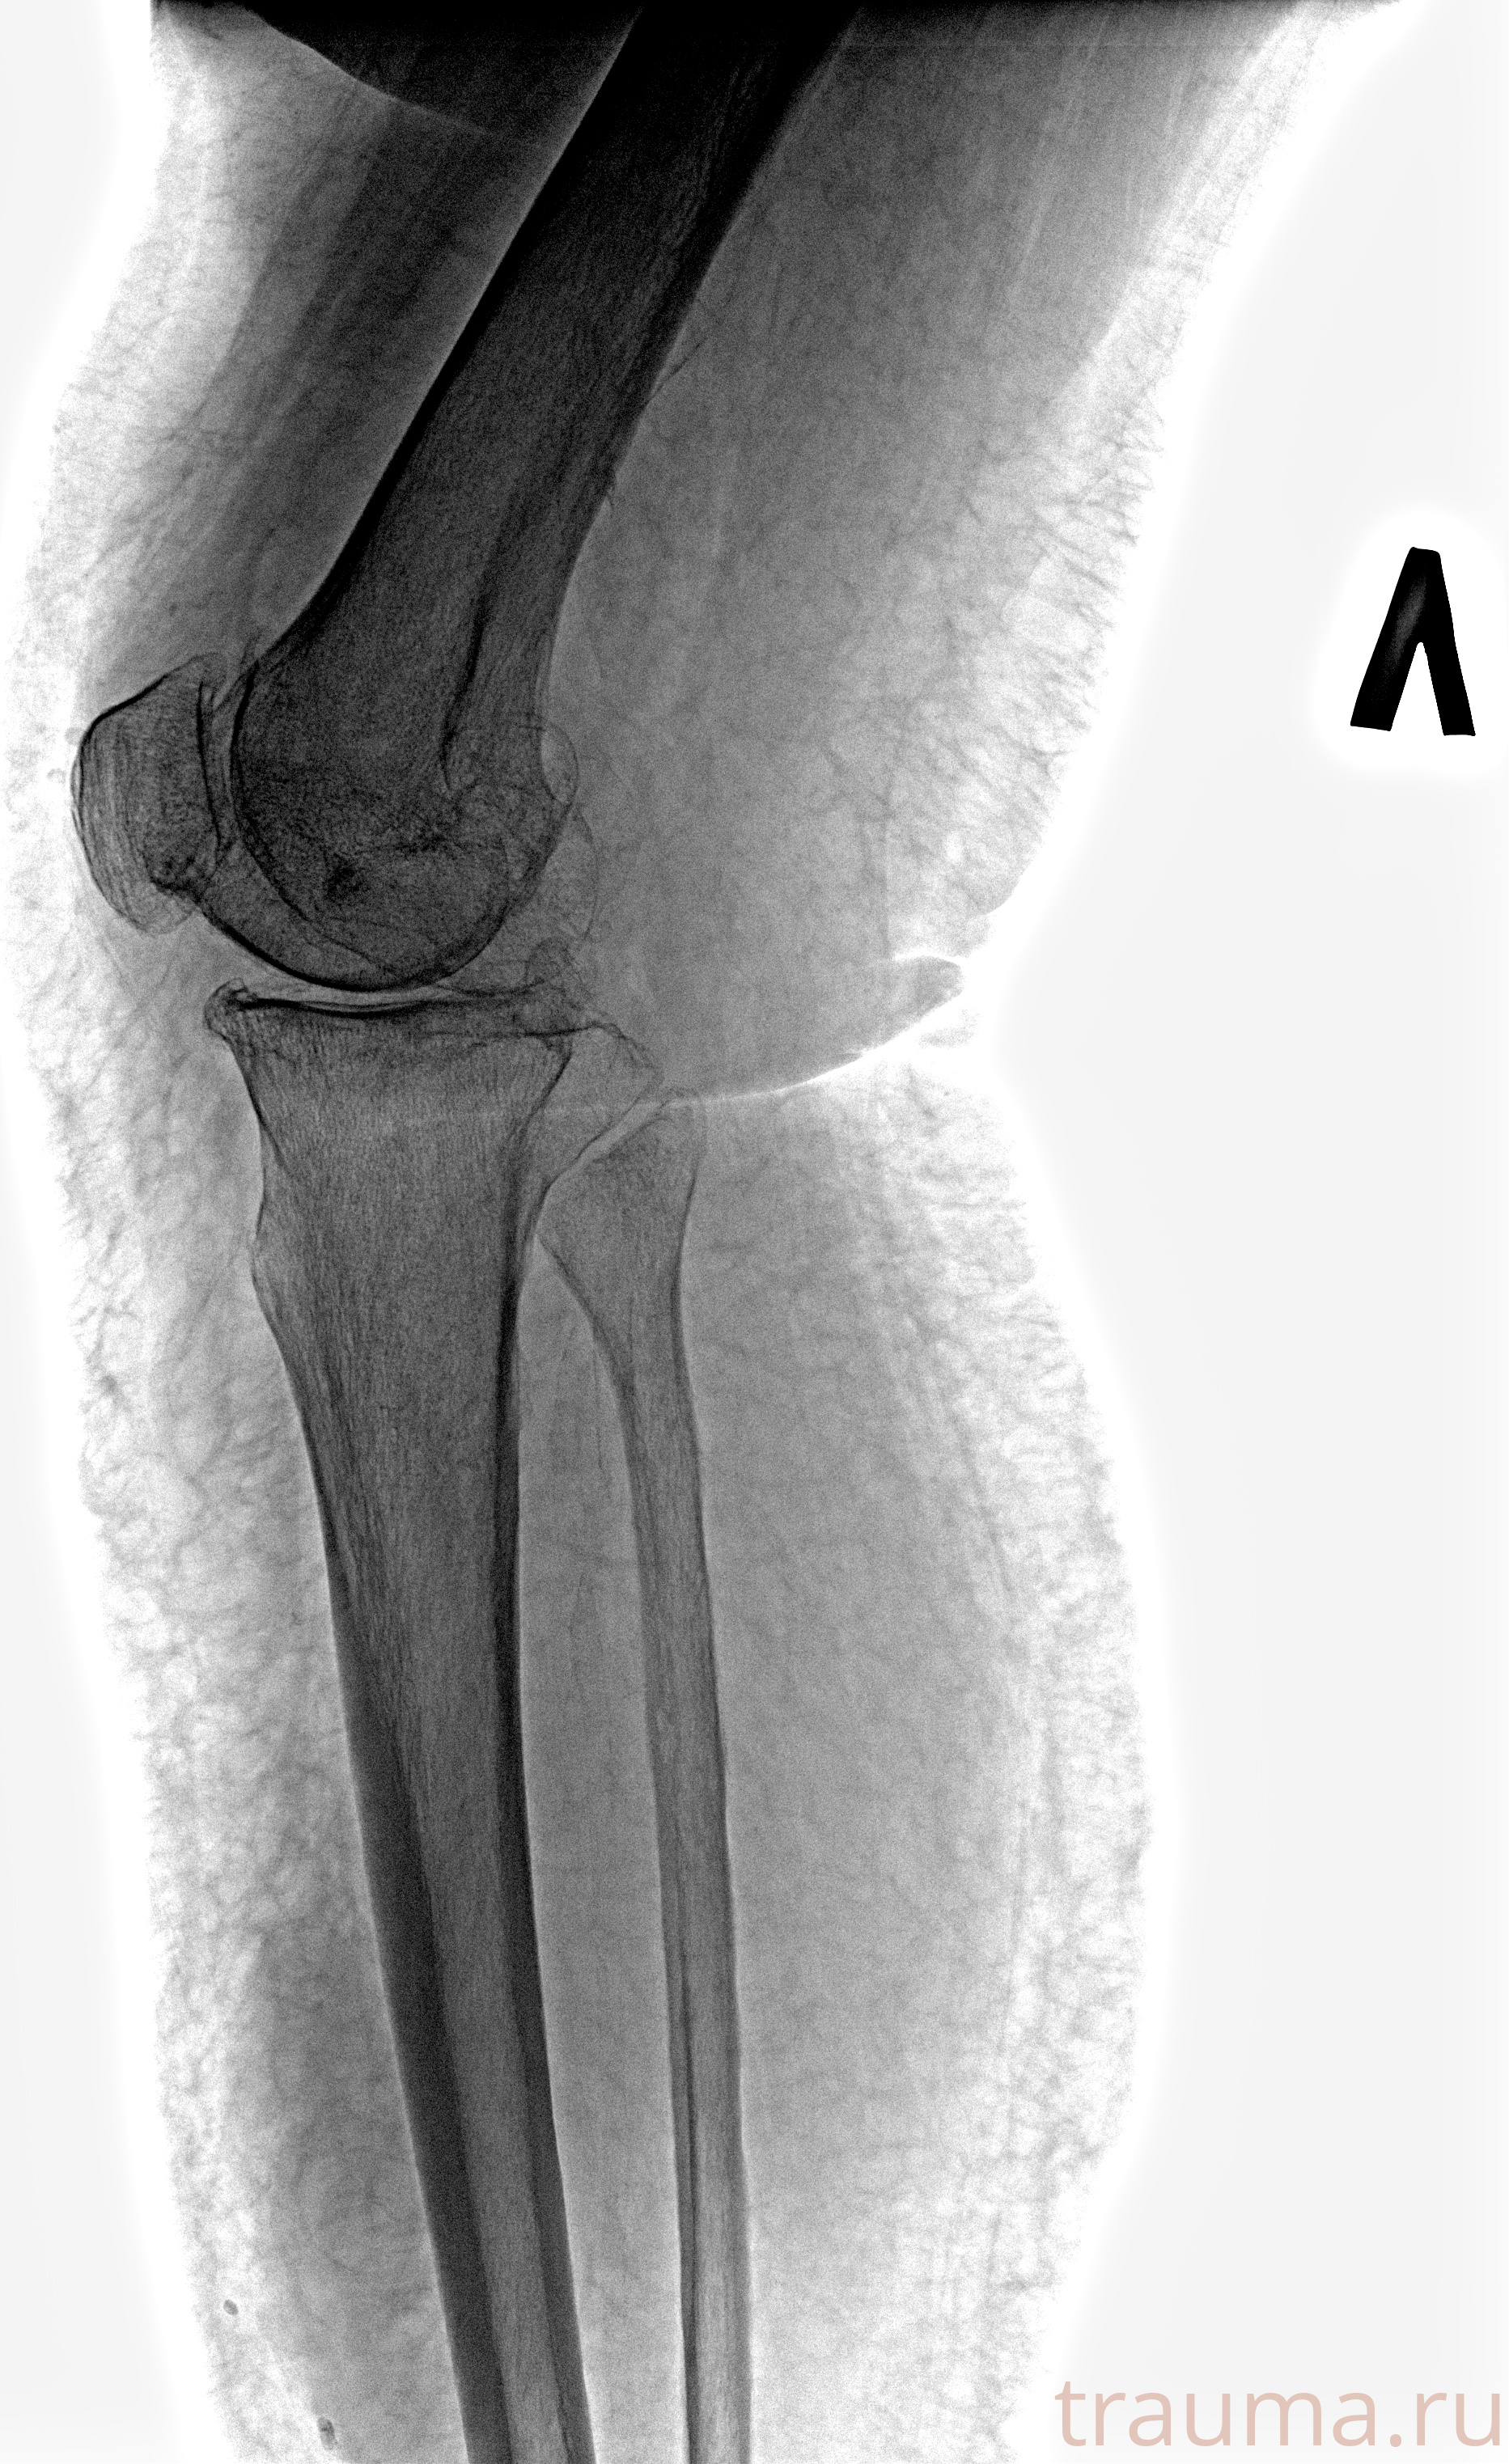

Рентген на дому: по вашему адресу приезжает врач-рентгенолог, травматолог-ортопед с мобильным рентгеновским аппаратом, проводит диагностику травмы или заболевания, делает необходимые рентгенограммы, дает рекомендации по дальнейшему лечению. Получить качественные снимки в домашних условиях возможно благодаря уникальной методике, разработанной МосРентген Центром для института  Склифосовского

при переломе шейки бедра и пневмонии от компании МосРентген Центр - партнера Института имени Склифосовского